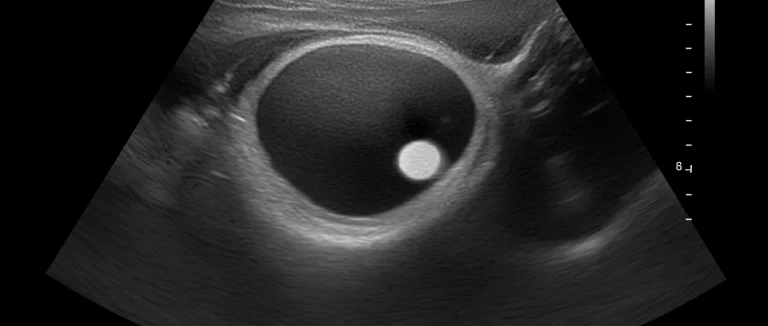

Если у пациента уже диагностирован нефролитиаз, появление вышеописанных признаков требует немедленного обследования. Анализ мочи поможет выявить бактериальный рост, а ультразвуковое исследование (УЗИ) или компьютерная томография (КТ) покажут расположение камней и степень их обструкции.

- УЗИ почек – первый шаг, позволяющий оценить размер и локализацию камня.

Для точной диагностики используют несколько методов: посев мочи определяет возбудителя и чувствительность к антибиотикам; УЗИ почек оценивает размер и локализацию камня; КТ с контрастом – золотой стандарт для выявления обструкции и сопутствующего воспаления. Дополнительно проводят биохимический анализ крови для оценки функции почек и наличия системного воспаления. Совмещение этих методов позволяет определить степень риска и выбрать оптимальную тактику лечения.